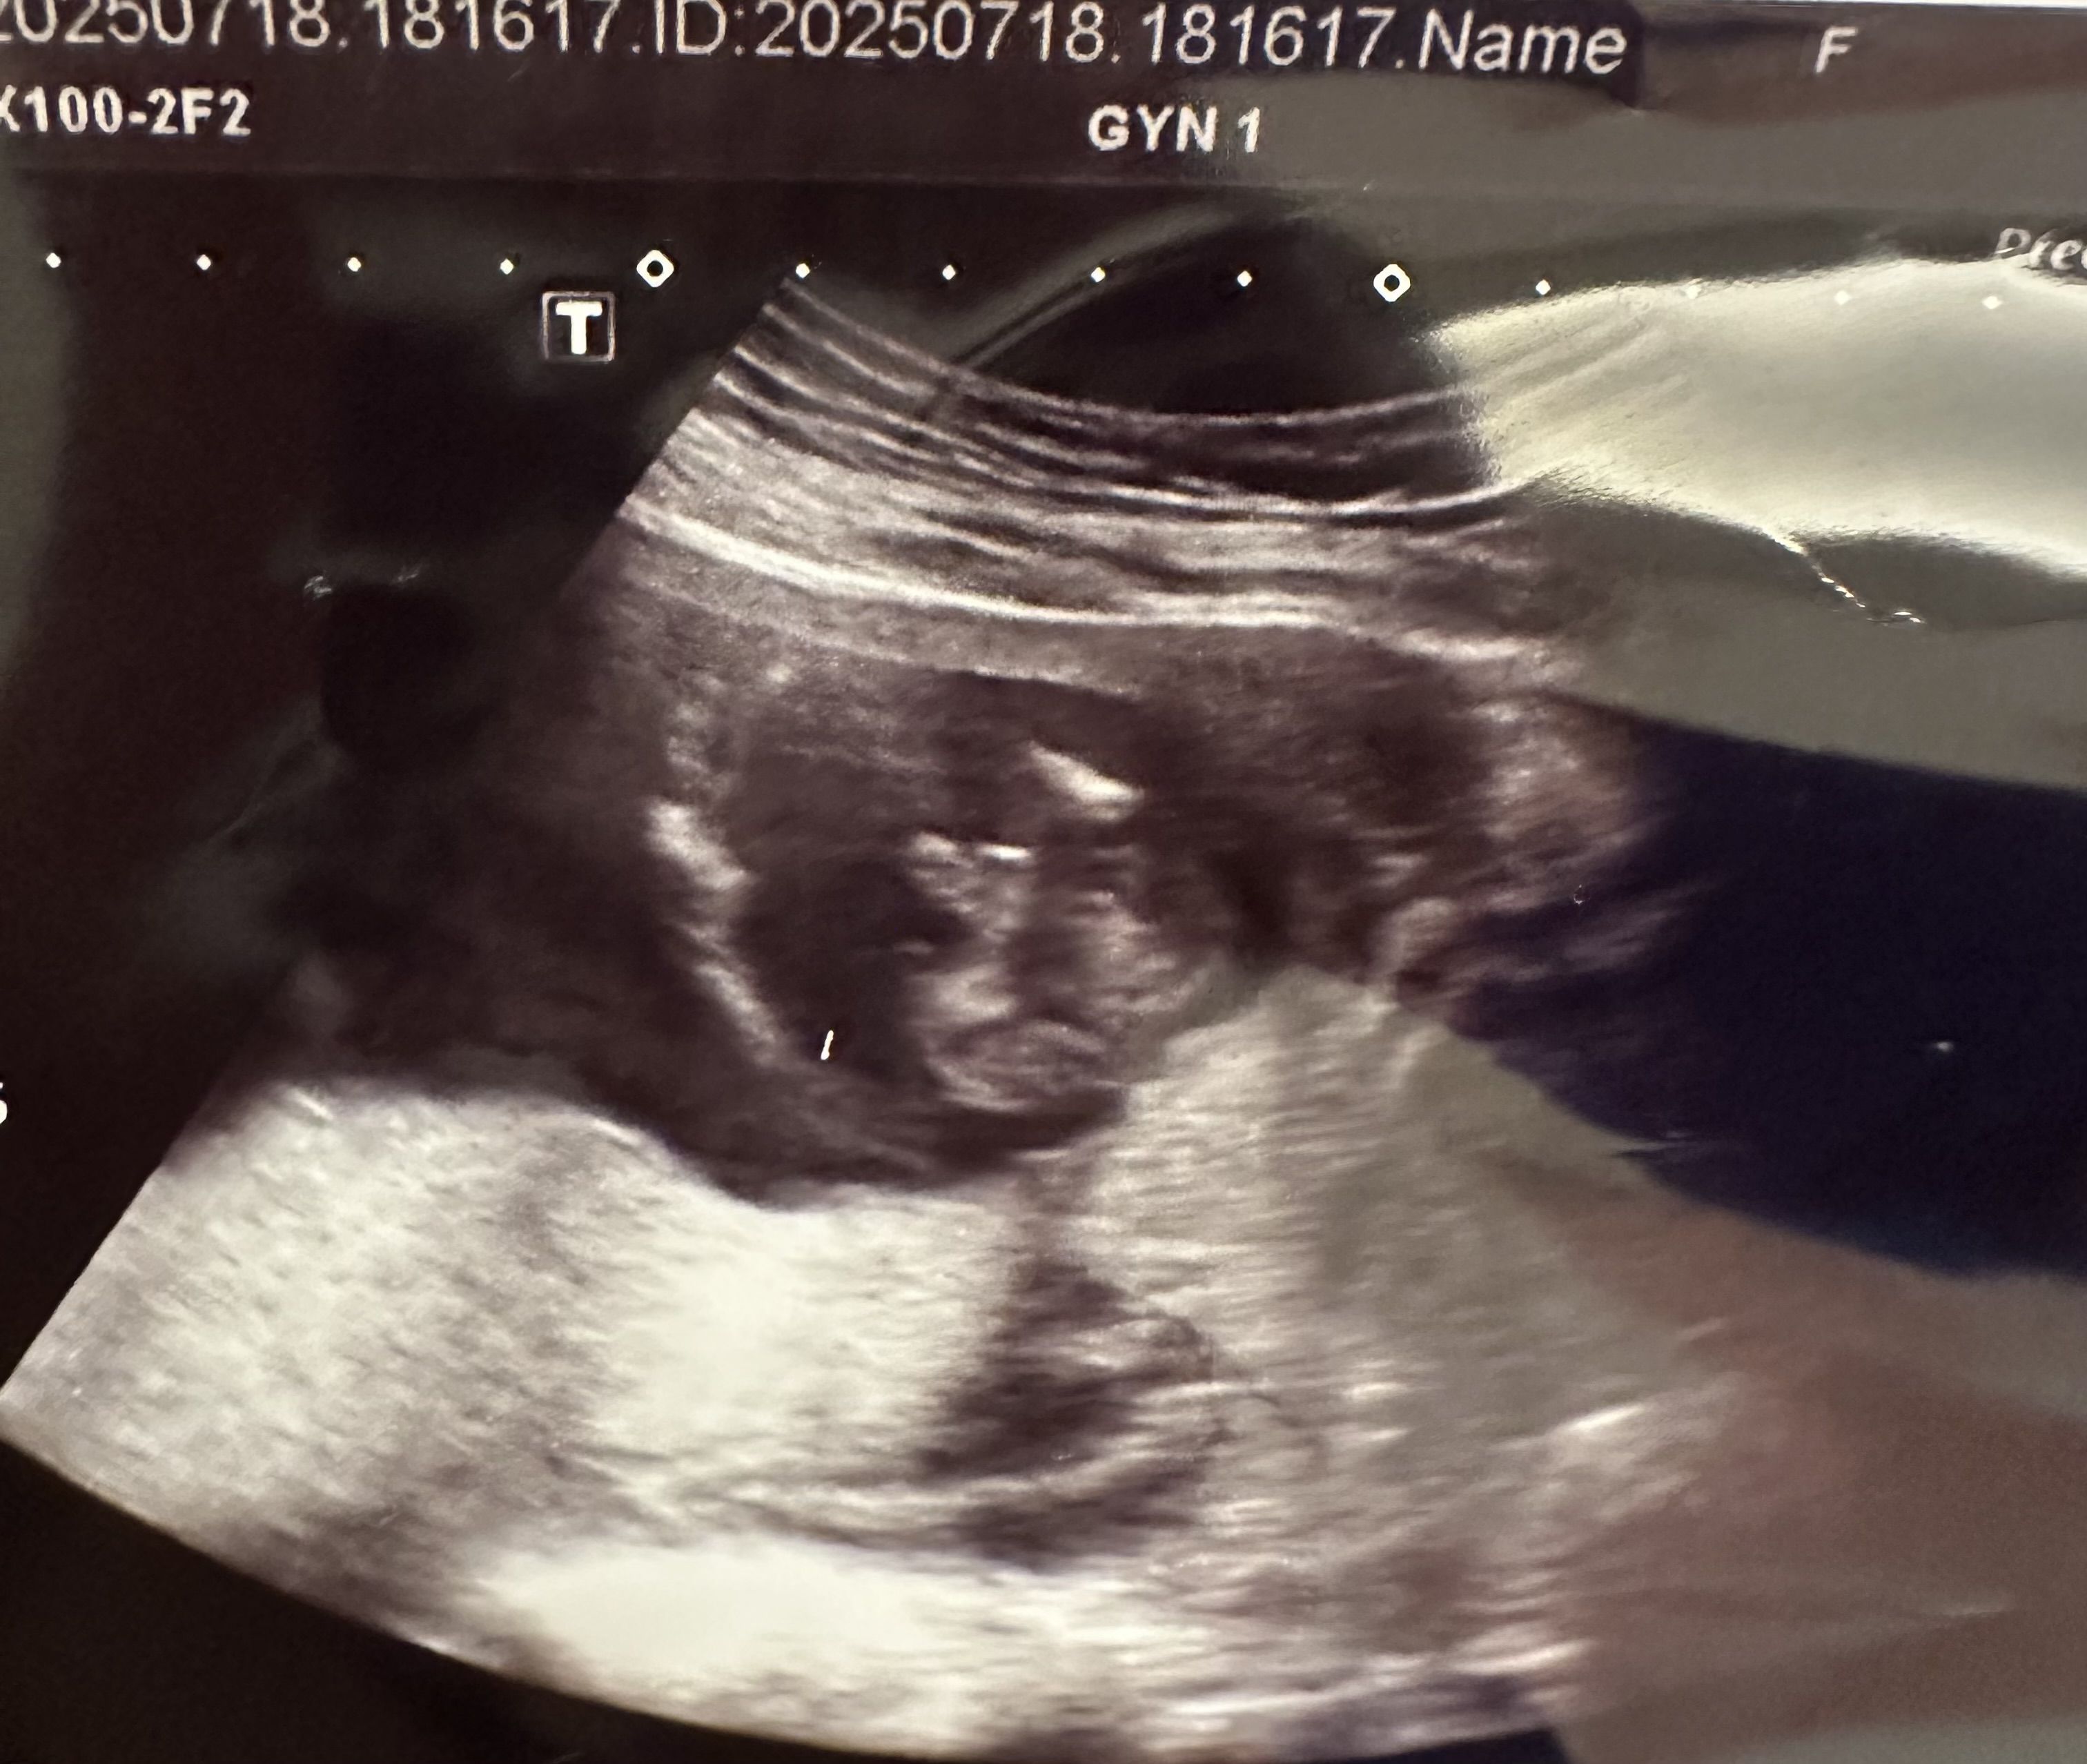

16+1週的時候產檢醫師有拍到寶寶生殖器說很明顯是男生

因為時間關係只能在高層次前辦性別趴,想請個位媽咪們幫忙看看超音波照片

還有想問看看有沒有20週男翻女的情形呢?